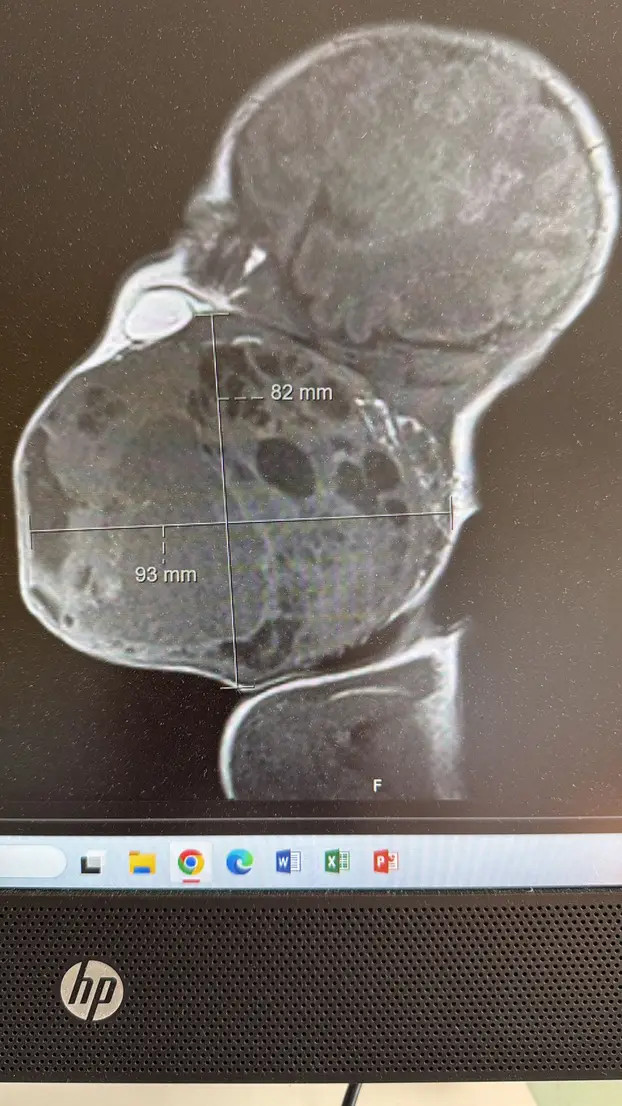

U trenutku kada je beba bila rođena do polovice, medici su primijetili ogroman tumor koji je potpuno blokirao dišne putove. Ova situacija je zahtijevala brzu i efikasnu reakciju multidisciplinarnog tima koji se sastojao od neuroloških, otorinolaringoloških, neonatoloških i neuroradioloških stručnjaka. U dokumentiranim izjavama iz bolnice, istaknuli su kako je njihova suradnja bila ključna u spašavanju života novorođenčeta. Ravnatelj KBC-a Zagreb, prof. dr. sc. Fran Borovečki, naglasio je da bolnicu čine ljudi, a ne zidovi, što dodatno oslikava važnost timskog rada u medicini. Ovaj slučaj osvijetlio je kako kolektivno znanje i vještine mogu napraviti razliku u najkritičnijim trenucima.

Prema riječima doc. dr. sc. Davida Ozretića, tumor je bio toliko velik da je prijetio potpunim zatvaranjem dišnog puta, a liječnici su znali da dijete neće moći disati nakon poroda. Ključni trenutak bio je osiguravanje dišnog puta dok je beba još bila u maternici. Tokom ovog izuzetno stresnog trenutka, doktori su uspješno postavili tubus u dušnik bebe, osiguravajući joj prohodnost disajnih puteva i mogućnost udisanja kisika prije nego što je porod završen. Tek nakon stabilizacije srčane aktivnosti, dovršen je porod, a pupkovina je prerezana, čime je dijete dobilo priliku za život.

Nakon što je beba rođena, uslijedila je zahtevna operacija odstranjivanja tumora koja je trajala više od dva sata. Ova operacija je bila posebno izazovna s obzirom na to da je dijete bilo staro samo nekoliko sati. Medicinski tim se suočio s nizom prepreka: uklanjanje tumora bez oštećenja okolnih tkiva, očuvanje vitalnih funkcija disanja, gutanja i potencijalnog govora. Ova kompleksnost zahvata zahtijevala je izuzetnu pažnju i vještinu, a rezultati su bili ohrabrujući. Histološki nalaz potvrdio je da je tumor u potpunosti uklonjen, a tumorski markeri su bili negativni, što znači da dijete sada smatraju izliječenim. Tim liječnika, predvođenim iskusnim kirurgom prof. dr. sc. Drago Prgometom, pokazao je nevjerojatnu predanost i stručnost, a njihova uspješna suradnja postavila je nove standarde u neonatalnoj hirurgiji.